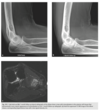

Anteroposterior view of the right foot

of the first patient shows soft-tissue swelling, ex-

tensive periarticular erosions with sclerotic borders,

overhanging edges in the first metatarsophalan-

geal joint, and preservation of the articular space

(Fig. 2.22.1, arrows). A lateral view of the right el-

bow in a different patient reveals marked soft-tissue

swelling and a faint radiopacity in the region of

the olecranon bursa. Minimal erosive changes are

present in the posterior surface of the olecranon

(Fig. 2.22.2, arrow).

Gout

The most common findings are punched-

out erosions with sclerotic borders and overhanging

cortical margins, referred to as overhanging edges or

margins. The erosions may be intraarticular, periar-

ticular, or located some distance from the joint. Soft-

tissue tophi, producing masses adjacent to the areas

of bony erosion, may occasionally contain faint

calcification within them. Generally, the articular

space is preserved, and periarticular osteopenia is

minimal. The olecranon bursa is the most common

site of gouty bursal involvement.